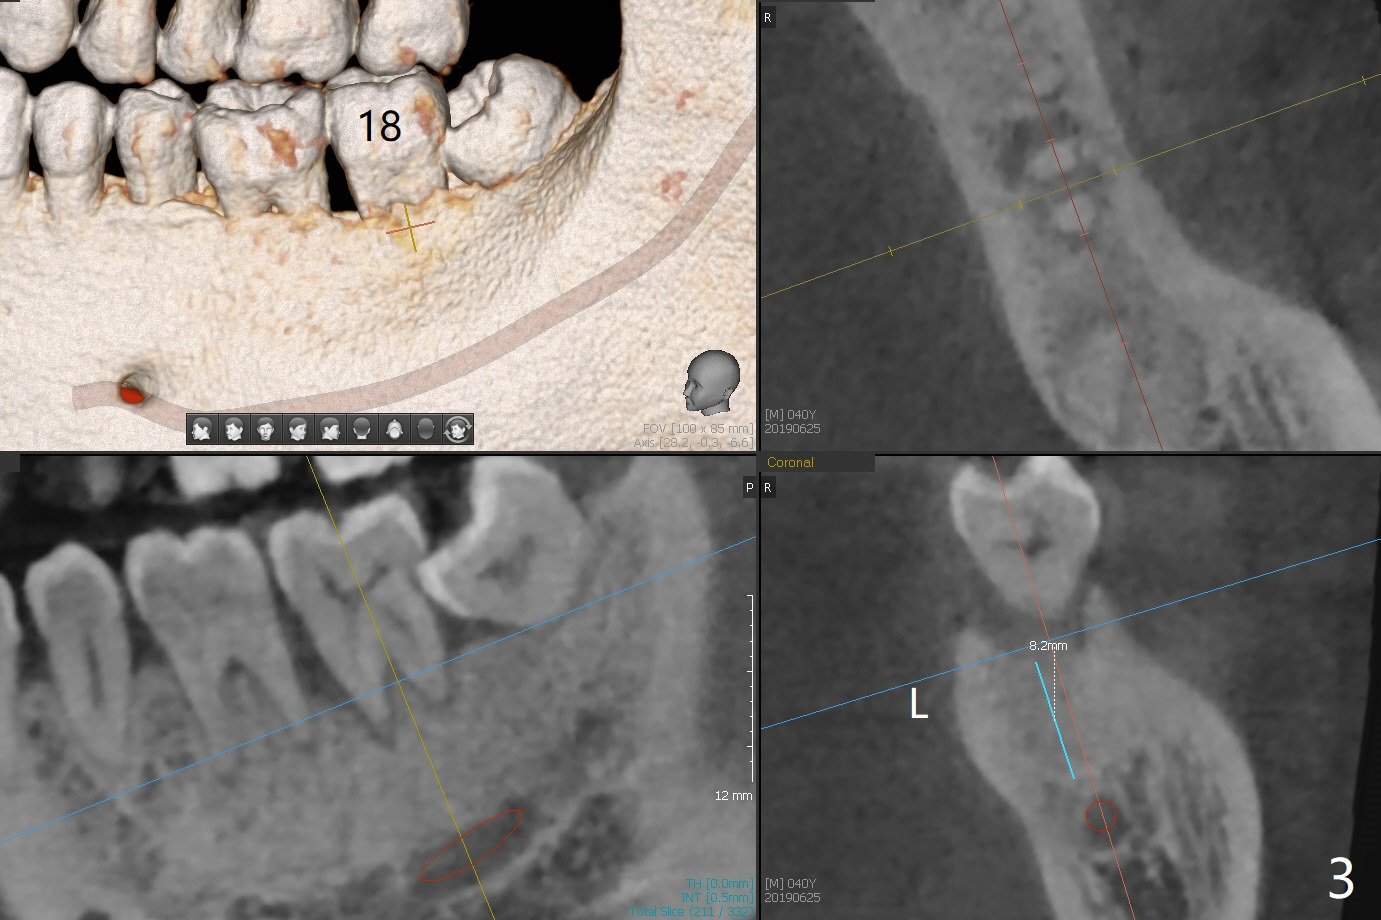

A 40-year-old man (smoker, 1ppd) is concerned about #31 mobility (Fig.1). Gross debridement is finished in his 1st appointment, while impression is taken for guide in his 2nd one. SRP has been scheduled for lower right quadrant with #31 extraction and immediate implant (Fig.2). The tooth #17 extraction will be postponed. The extraction may lead to mobility of the tooth #18, although SRP for the other 3 quadrant will be scheduled 1 week post #31 surgery. Smoke reduction is encouraged. When the crown is delivered at #31 one year later, the tooth #18 is loose (Fig.3) with lingual fistula. Since bone loss is more severe lingual (L *), a 5x10 mm immediate implant will be placed buccal (Fig.4). The tooth #17 will be kept as a distal stop for guide and extracted after #18 implant placement. Bone loss at #18 is more severe with mobility 15 months later; a shorter implant will be placed (Fig.5). After local scaling & root planing of the distal surface of #19 and application of Endogain, place sticky bone (red circle). Insert Collagen or Osteogen Plug in the #17 sockets.